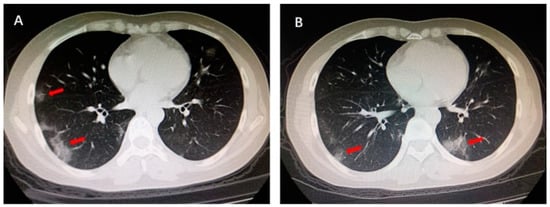

The LIME interpretable model was used for the explainability of lung pulmonary disease COVID-19. After understanding the manifest info file of the COVID-CT dataset, we found some recurrence of the positive COVID CT images that is published in the 2020 International Journal. Figure 5 shows the region highlighted by the arrow by one of the verified doctors, and he describes the reasons that caused the COVID-19. This red arrow shows the multiple patchy ground-glass opacities in bilateral subpleural areas. These are the main features of the CT images that took part in the COVID-19 classification result.

Figure 5.

Multiple patchy glass ground opacities in bilateral subpleural areas (red arrow).

This research achieves the main goal using the LIME interpretable model. Further, results are evaluated using a recurrence image to verify model authenticity by cross validation of experts as shown in Figure 7.

Figure 7.

Before: Ground glass opacities highlighted by doctor, after: Same area highlighted by our model.

Along with its quantitative solid performance, the proposed model’s explainability is also promising. To enhance the prediction to be more explainable, the activation maps are extracted by the developed method’s explainable module, which we visualized in Figure 7. It can be seen that the proposed method would make a positive prediction by focusing on the most important section of the CXR image, which can be designated as the bilateral subpleural areas that show the ground glass opacities of the lungs. Furthermore, rather than focusing solely on the image’s most important regions, we also consider the local regional contribution to the forecast. As previously stated, the input images were separated into many super-pixels, each of which had a similar visual pattern. This method highlighted those super-pixels in each image that greatly contributed to the prediction, and we can see that the regions with glass opacities are clearly highlighted for such a prediction. The comparative analysis of different XAI systems’ clinical features is available in Table 7. This research selects more clinical features to be explained in the developed framework and provides greater explainability than the other available methods. In this research, the developed explainable AI framework provides an explanation of local and global features. As a result, it reveals that diseased areas can be easily identified using this system. The proposed method explains pulmonary disease identification that can be used as a valuable diagnostic tool for doctors.